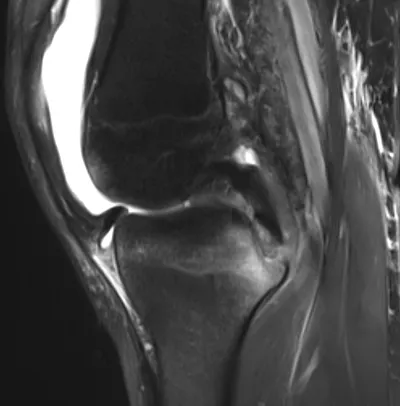

PCL Radiology Images

Browse 3 medical images tagged with pcl. This collection includes various imaging modalities for medical education and reference.

- This collection contains 3 radiology images related to pcl, including various imaging modalities such as X-rays, MRIs, CT scans, and ultrasound images commonly used in medical diagnosis and education.